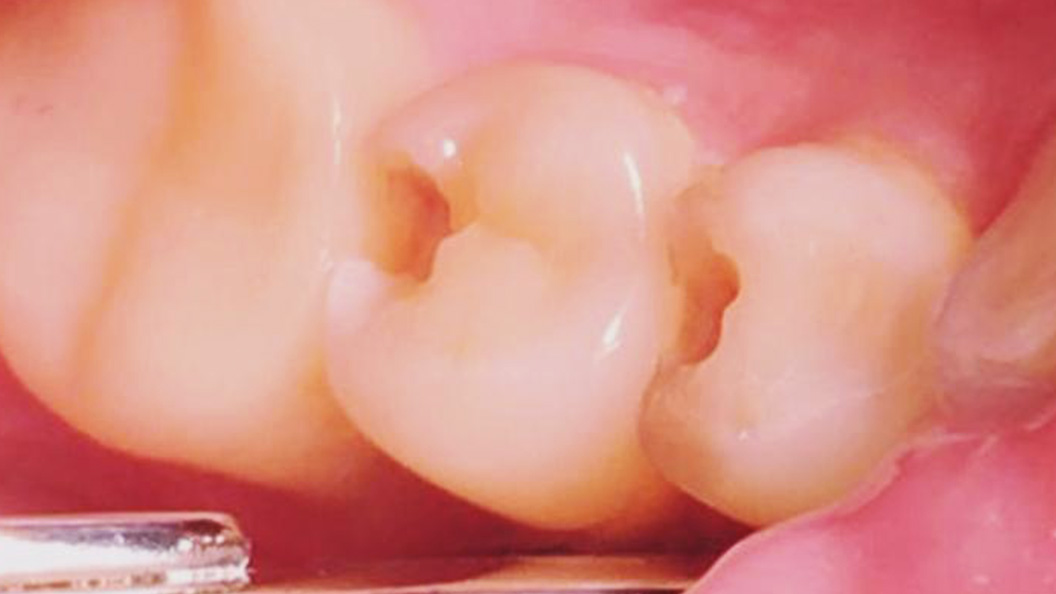

До и после лечения

Пациентка обратилась в «Стоматологию Комфорта» с жалобами на выпадение пломб зубов 44 и 45, болезненную реакцию на холодное и застревание пищи. В результате обследования врач Похилько Надежда Геннадьевна обнаружила глубокий кариес в районе зубов 44 и 45. Принято решение провести лечение с использованием композита светового отверждения Estelite.

Глубокий кариес зачастую проявляется ноющими болями, значительными углублениями на эмали и неприятным запахом изо рта. Такое заболевание поражает не только эмаль, но и глубокие слои дентина, граничащего с пульпой. Отсутствие лечения приводит к развитию пульпита, периодонтита, а также потере зубов.

Ход лечения:

- проведение местной анестезии;

- вскрытие кариозной полости, её очищение и обработка;

- установка пломбы из композита светового отверждения Estelite.